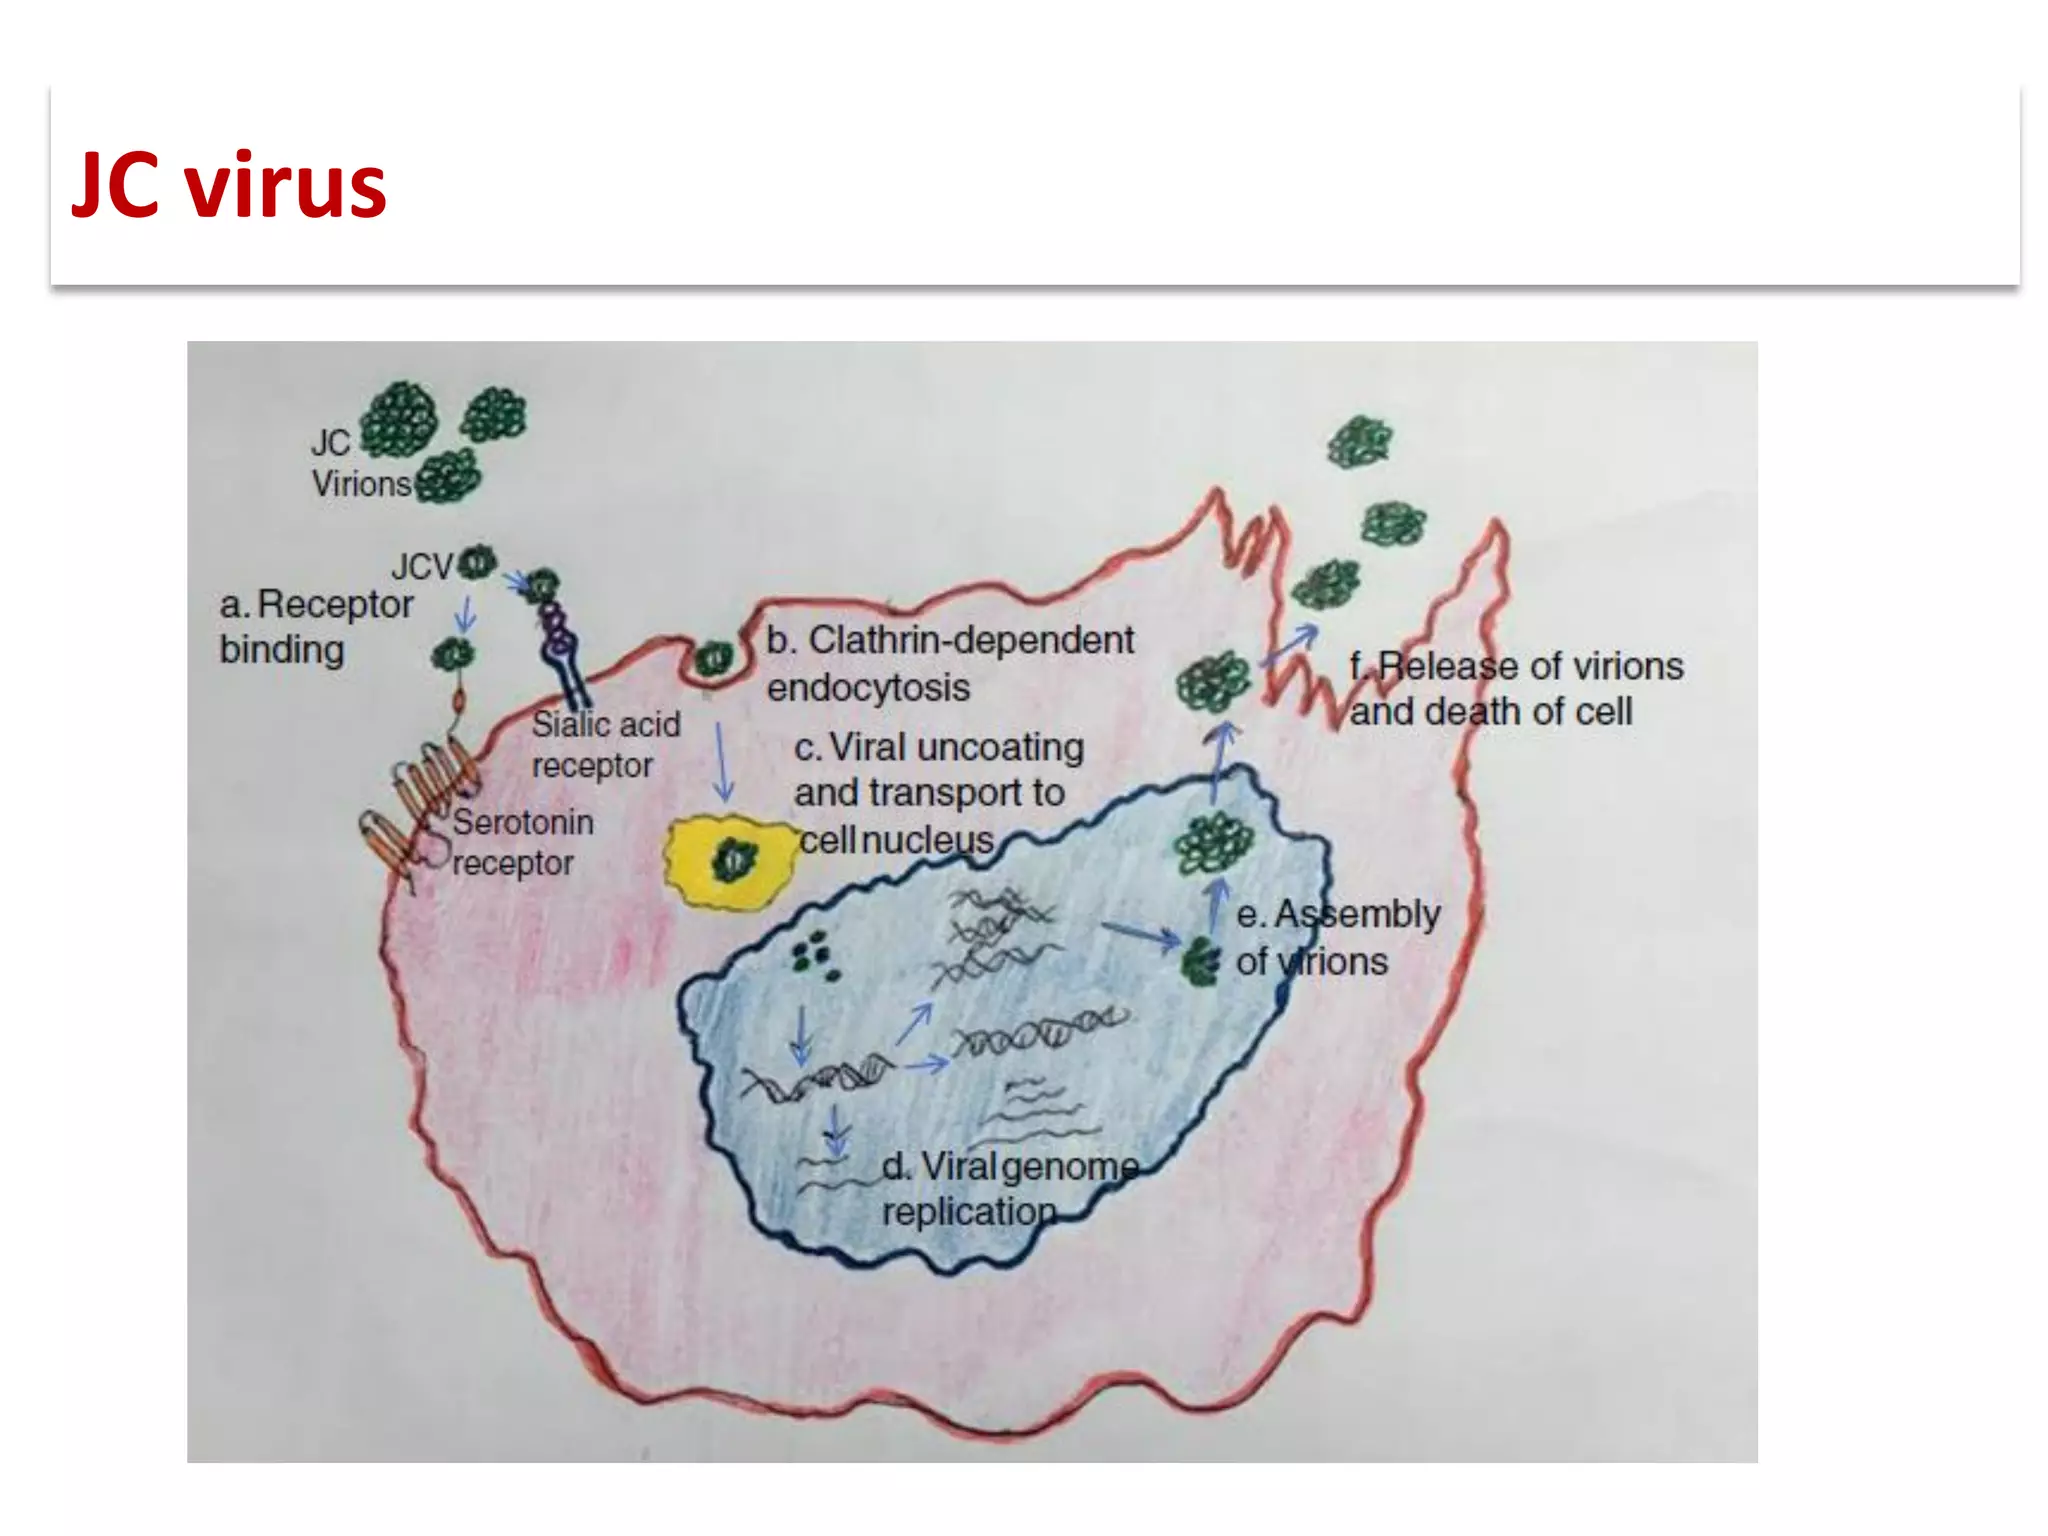

![▪ John Cunningham virus (JCV) is a

double-stranded DNA

polyomavirus.

▪ Takes its name from the initials of

the patient from whom it was

first isolated.

▪ PML was initially described in

patients with underlying B-cell

lymphoproliferative disorders [1]

JC virus](https://image.slidesharecdn.com/pml-220423195132/75/Progressive-multifocal-leukoencephalopathy-PML-2-2048.jpg)